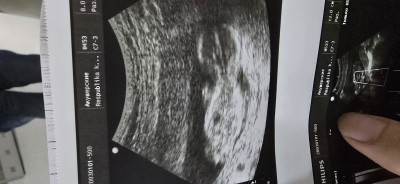

Ultrason Görüntüleri ile Cinsiyet Tahmini Yapmak Mümkün Mü?

Salam.Cinsiyyet tahmini yapmak mumkundurmu? Ultrason goruntulerine esasen.Hal hazirda 17+4 heftedir.Ultrason 13+4 heftenin goruntusudur

Çıkıntısı var gibi erkege benzettim ben